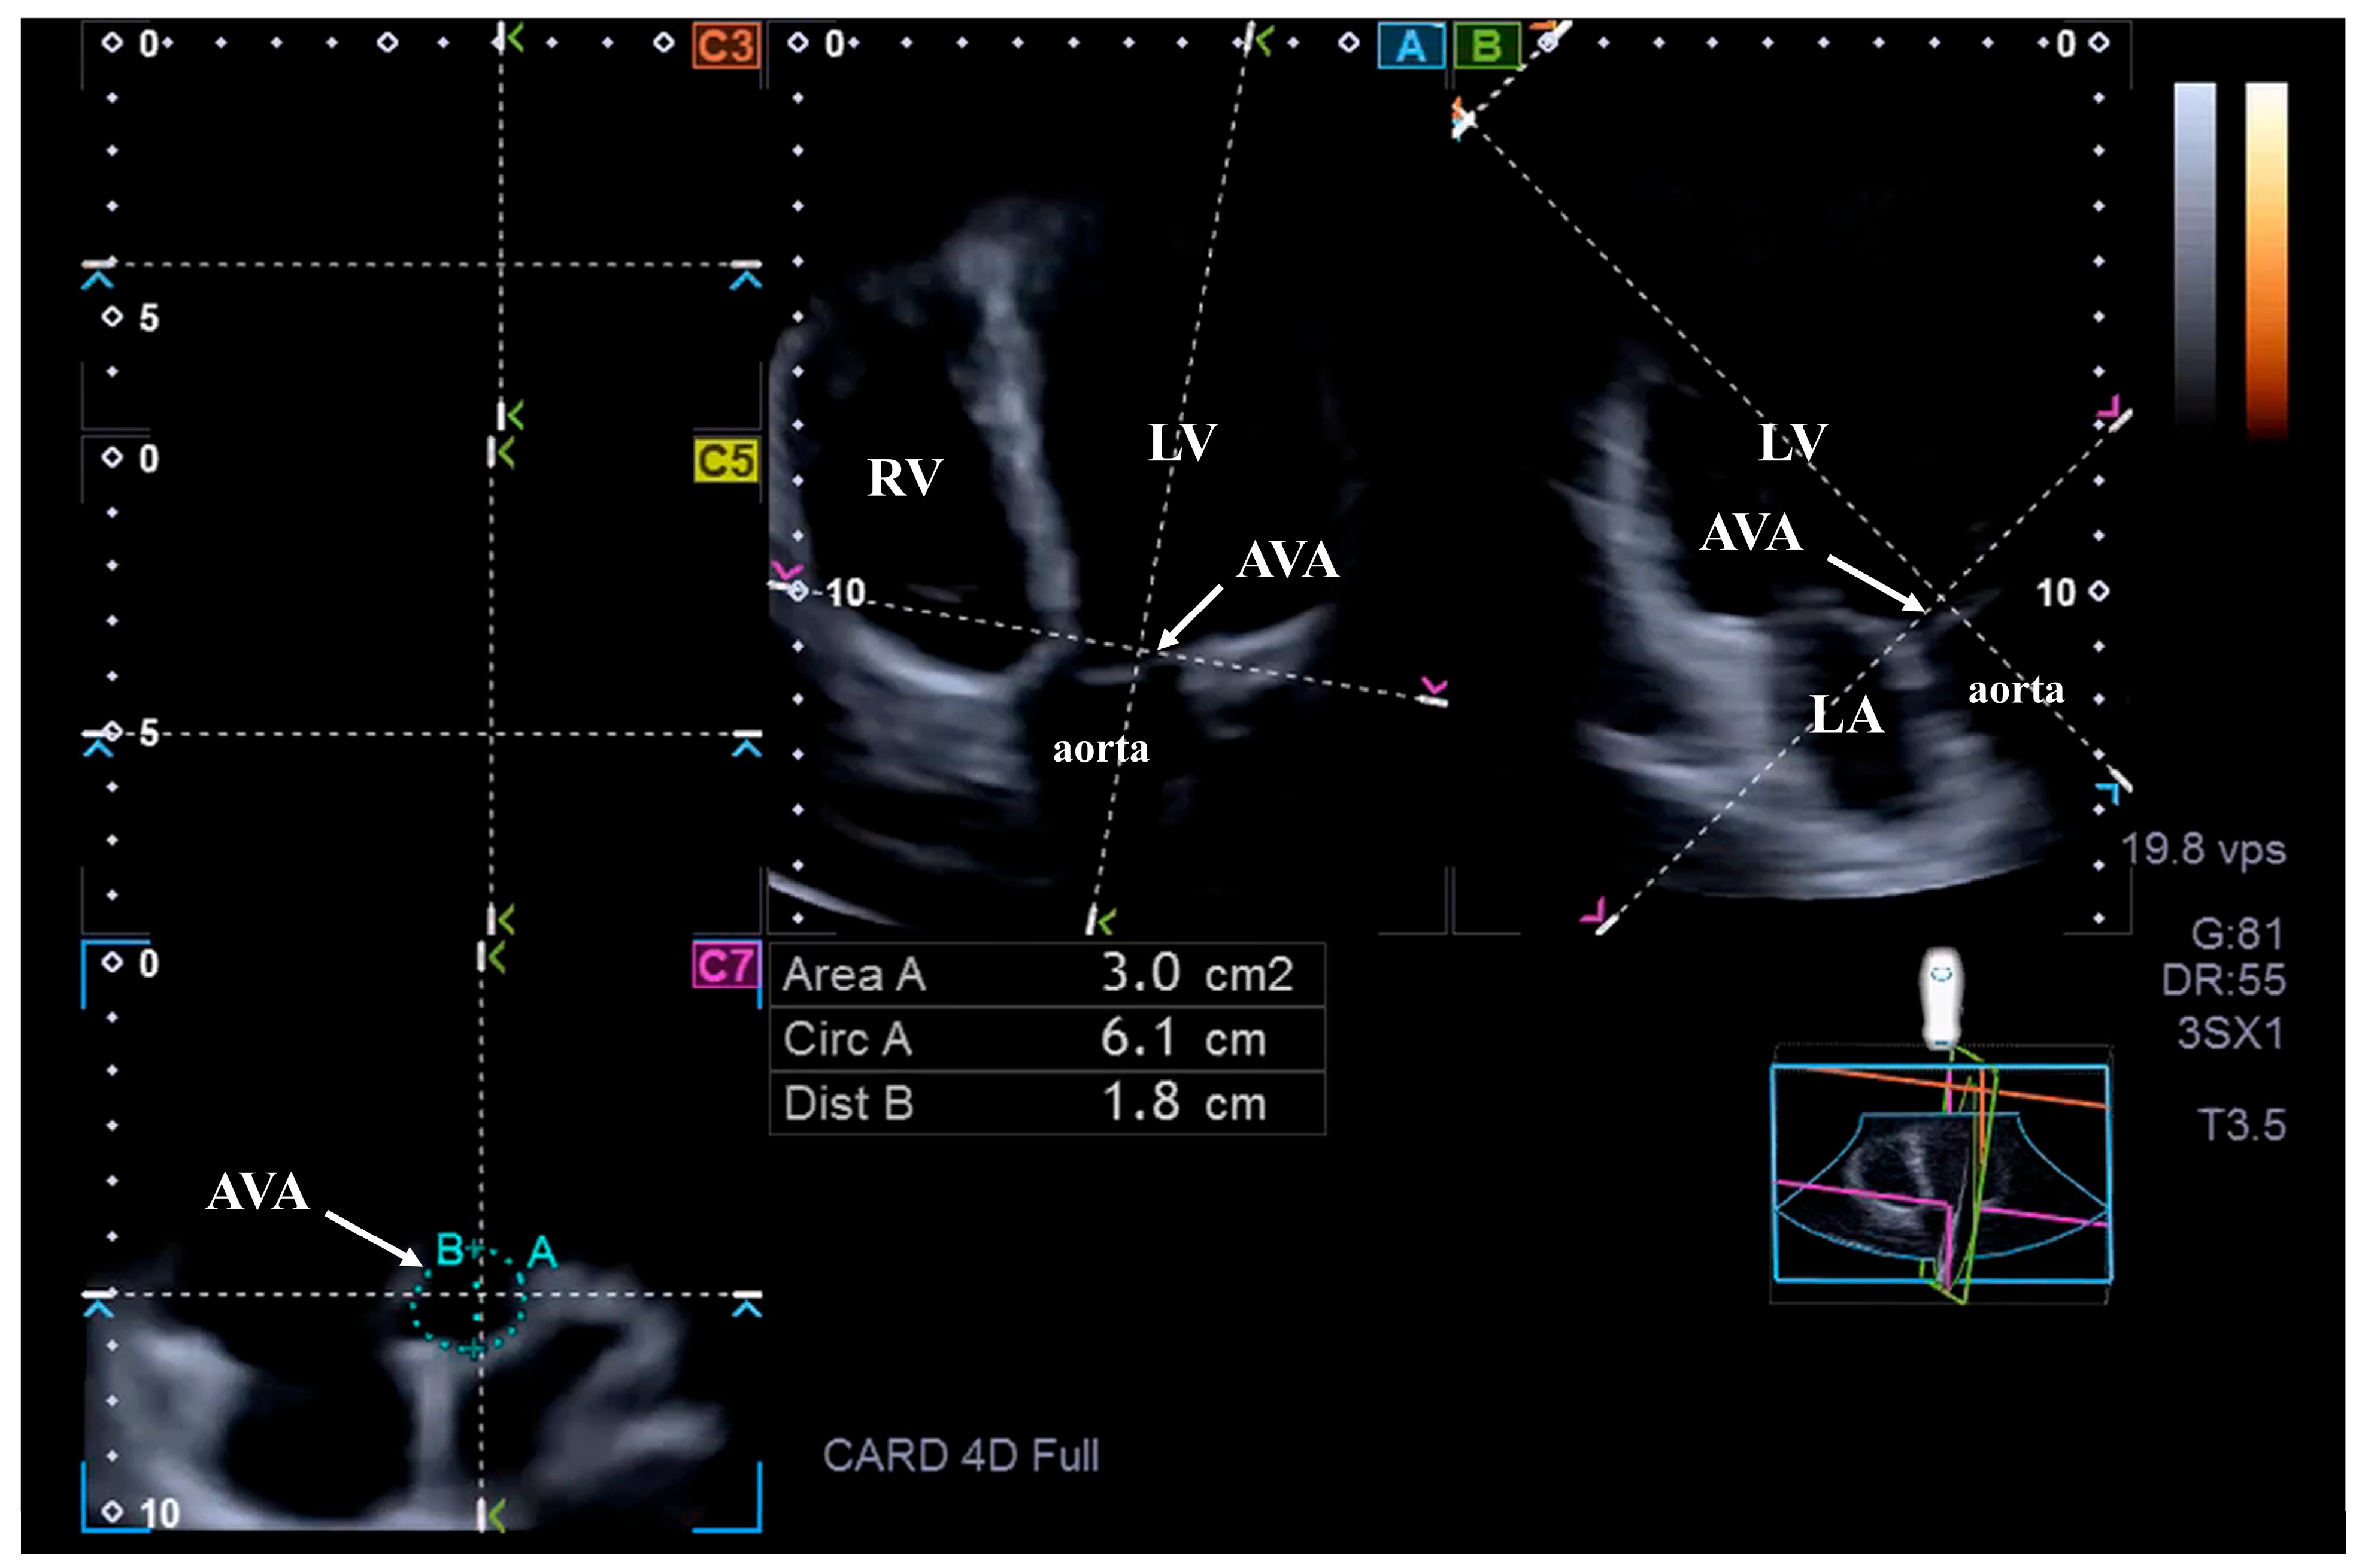

2.3. Three-Dimensional Speckle-Tracking Echocardiography

3.3. Three-Dimensional Speckle-Tracking Echocardiography

3.4. Reproducibility of 3DSTE-Derived AVA Assessments